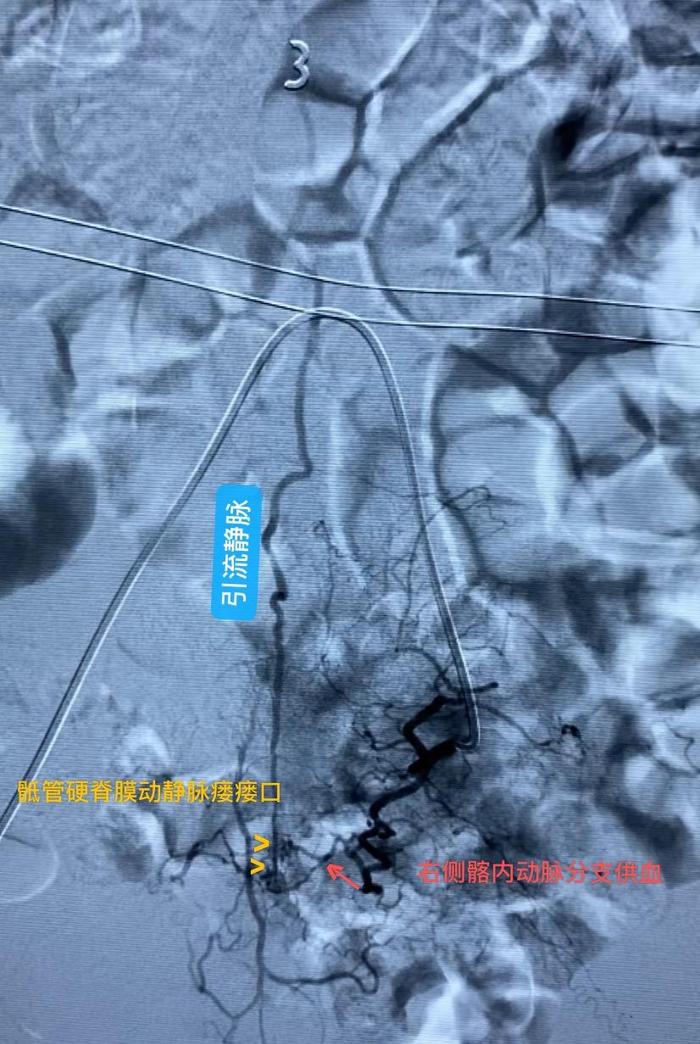

为积极挽救患者脊髓神经功能,戴大伟副主任医师团队第一时间收治患者入院,行全脊髓血管DSA造影明确左侧髂内动脉分支动脉供血的S1-2骶管硬脊膜动静脉瘘(SDAVF)

术中准确找到SDAVF瘘口及引流静脉术后复查DSA,SDAVF瘘口以及引流静脉完全不显影,患者双下肢肌力和感觉有很大进步,证实了手术的成功。